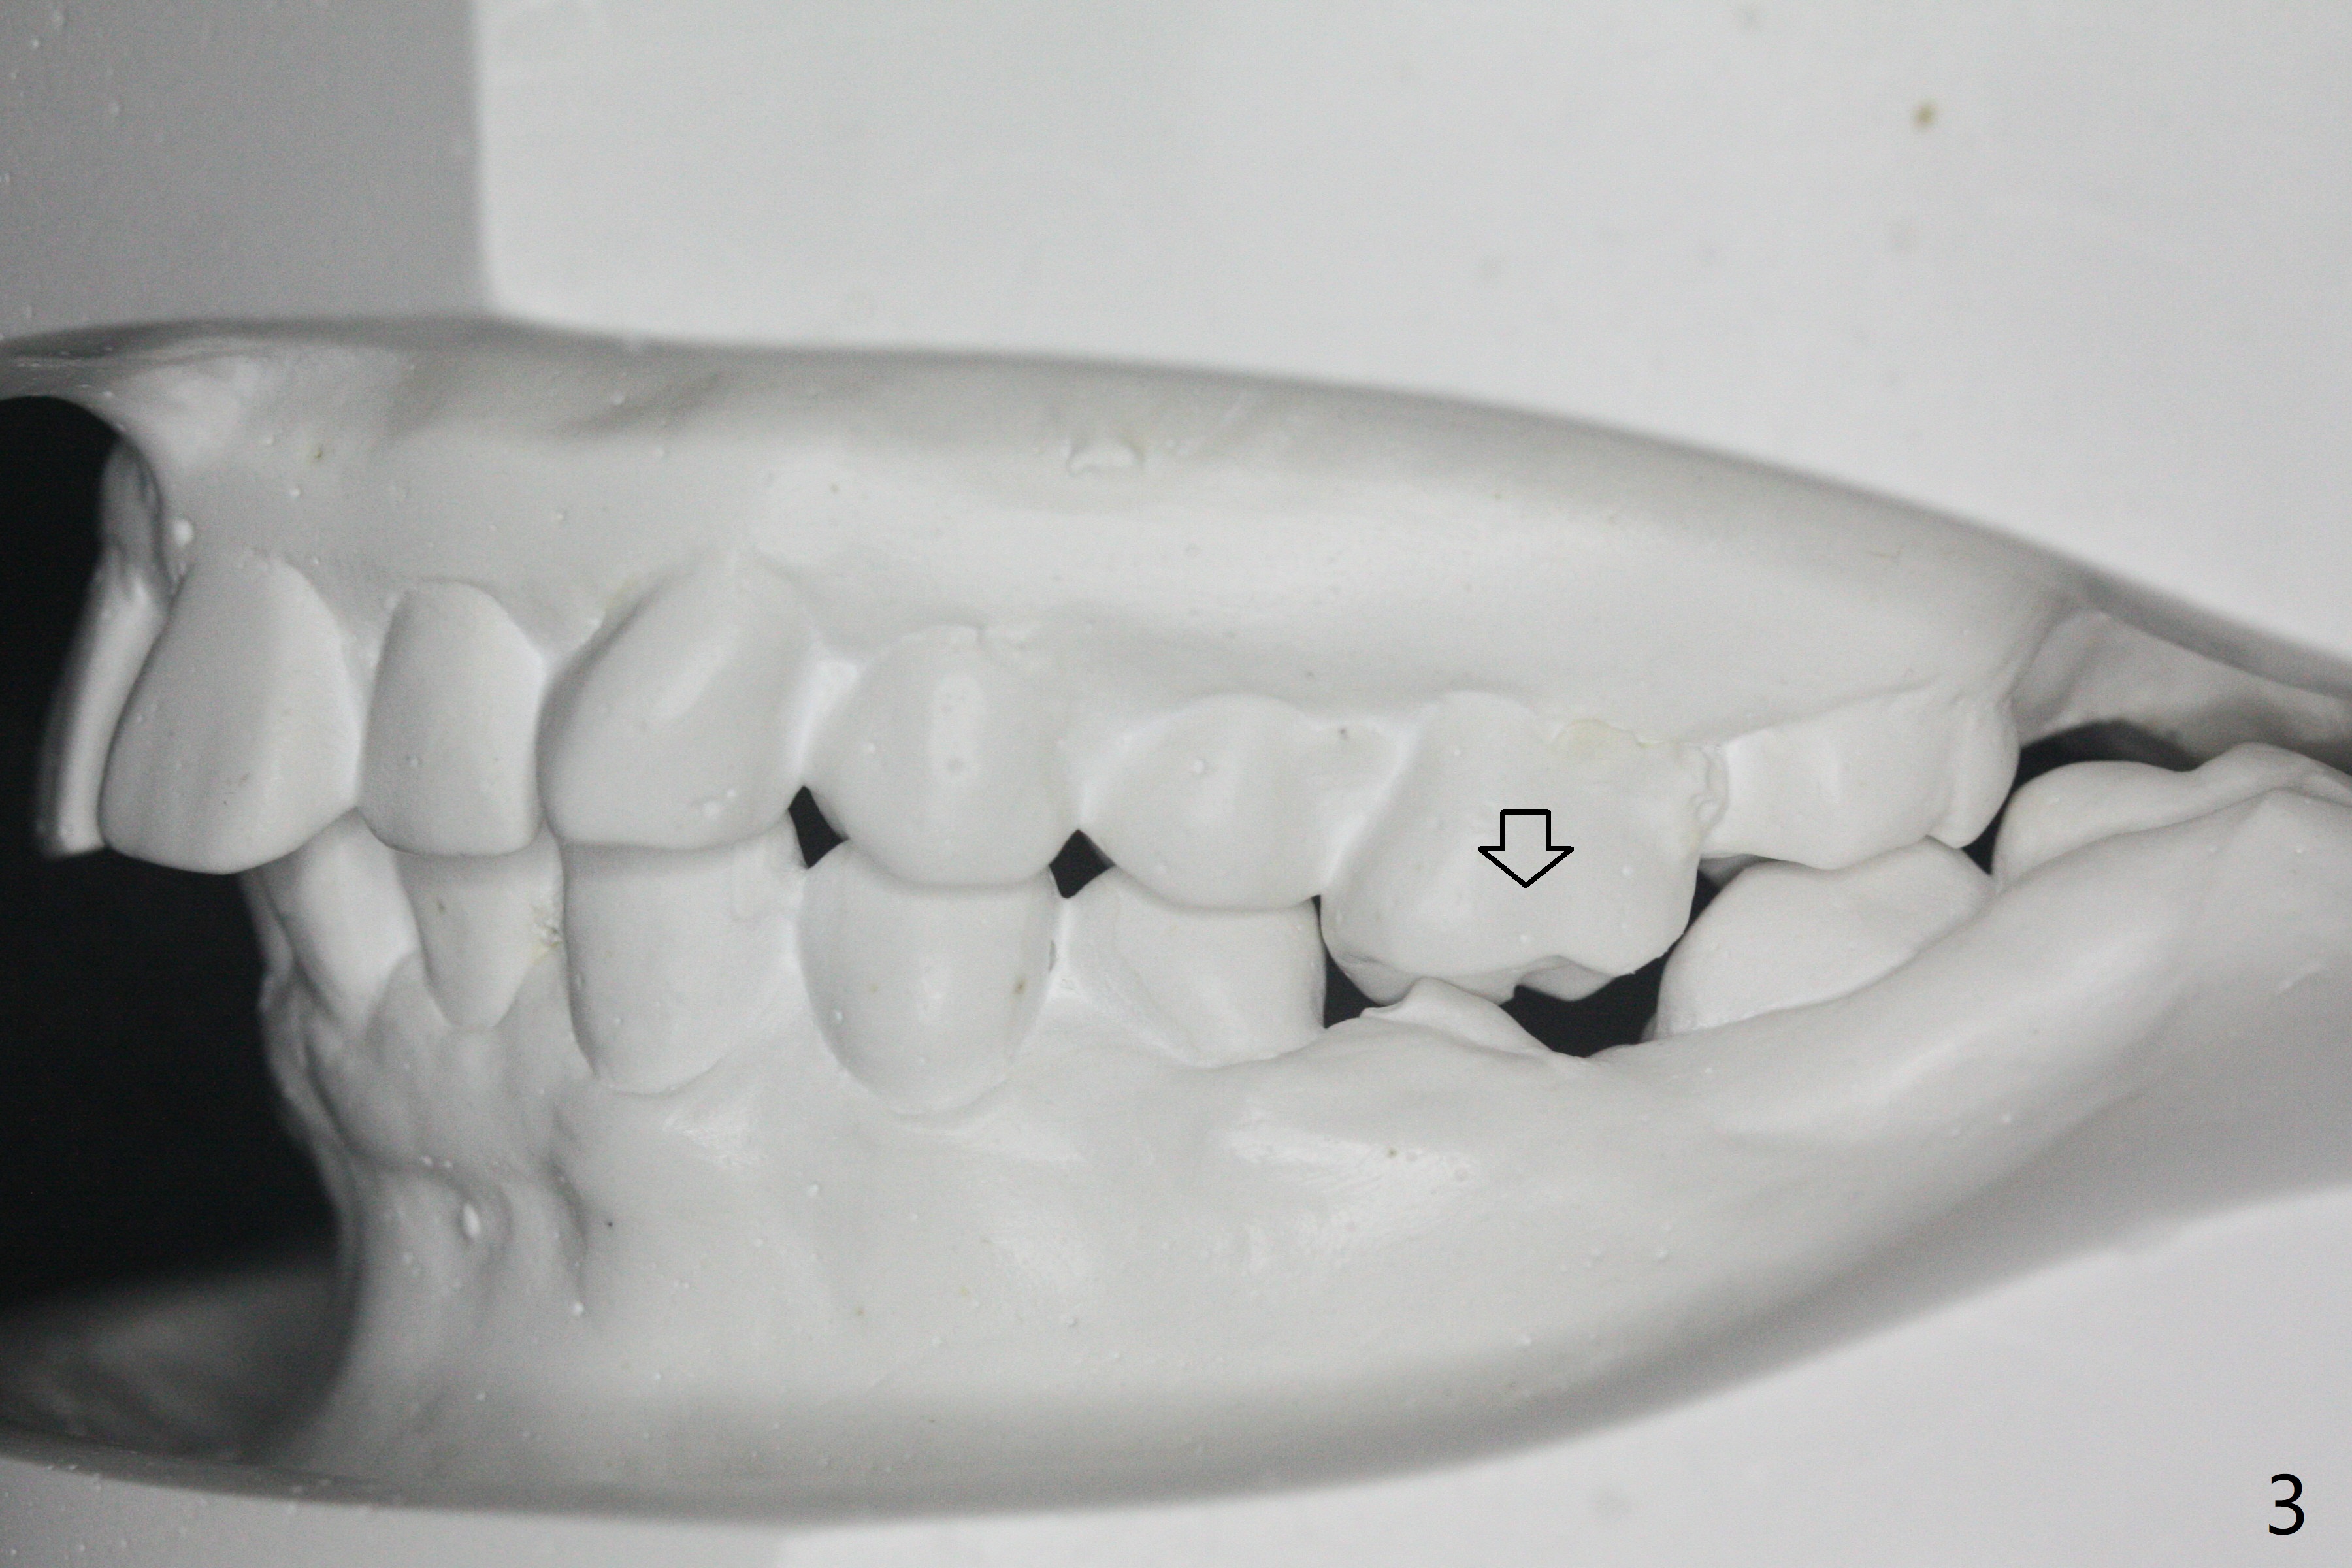

31岁女,牙周炎,安格氏二类错𬌗(图一至八),深洗后,同意牙齿矫正,但是要求保留左下智齿,前移7,8,取代6,左上6过度萌出(图三:箭头)。

初步计划:第一期安置矫正器,排列,建立正常前牙覆合覆盖,二类牵拉。尽量竖直左下7,8(图十一:白色轮廓);使用两个微型植体(图九:黑线(两个植体之间放置power chain(红线)))压入左上6(图十(圆圈:近中微型植体),与图三对比),为左下7近中移位(红色箭头)创造空间。

第二期在左下4和5之间植入微型植体作为支抗(图十一:红色),利用7远中长勾(粉红色)和橡皮筋,先让7平行近中移位,控制根torque。A 31-year-old woman with Class II Division I malocclusion requests orthodontic treatment without extraction of LL8. U8s and LL6 have been extracted with SRP. The 1st stage will be alignment , intrusion of UL6, upright of LL7 and 8 and correction of Class II malocclusion using double twin.